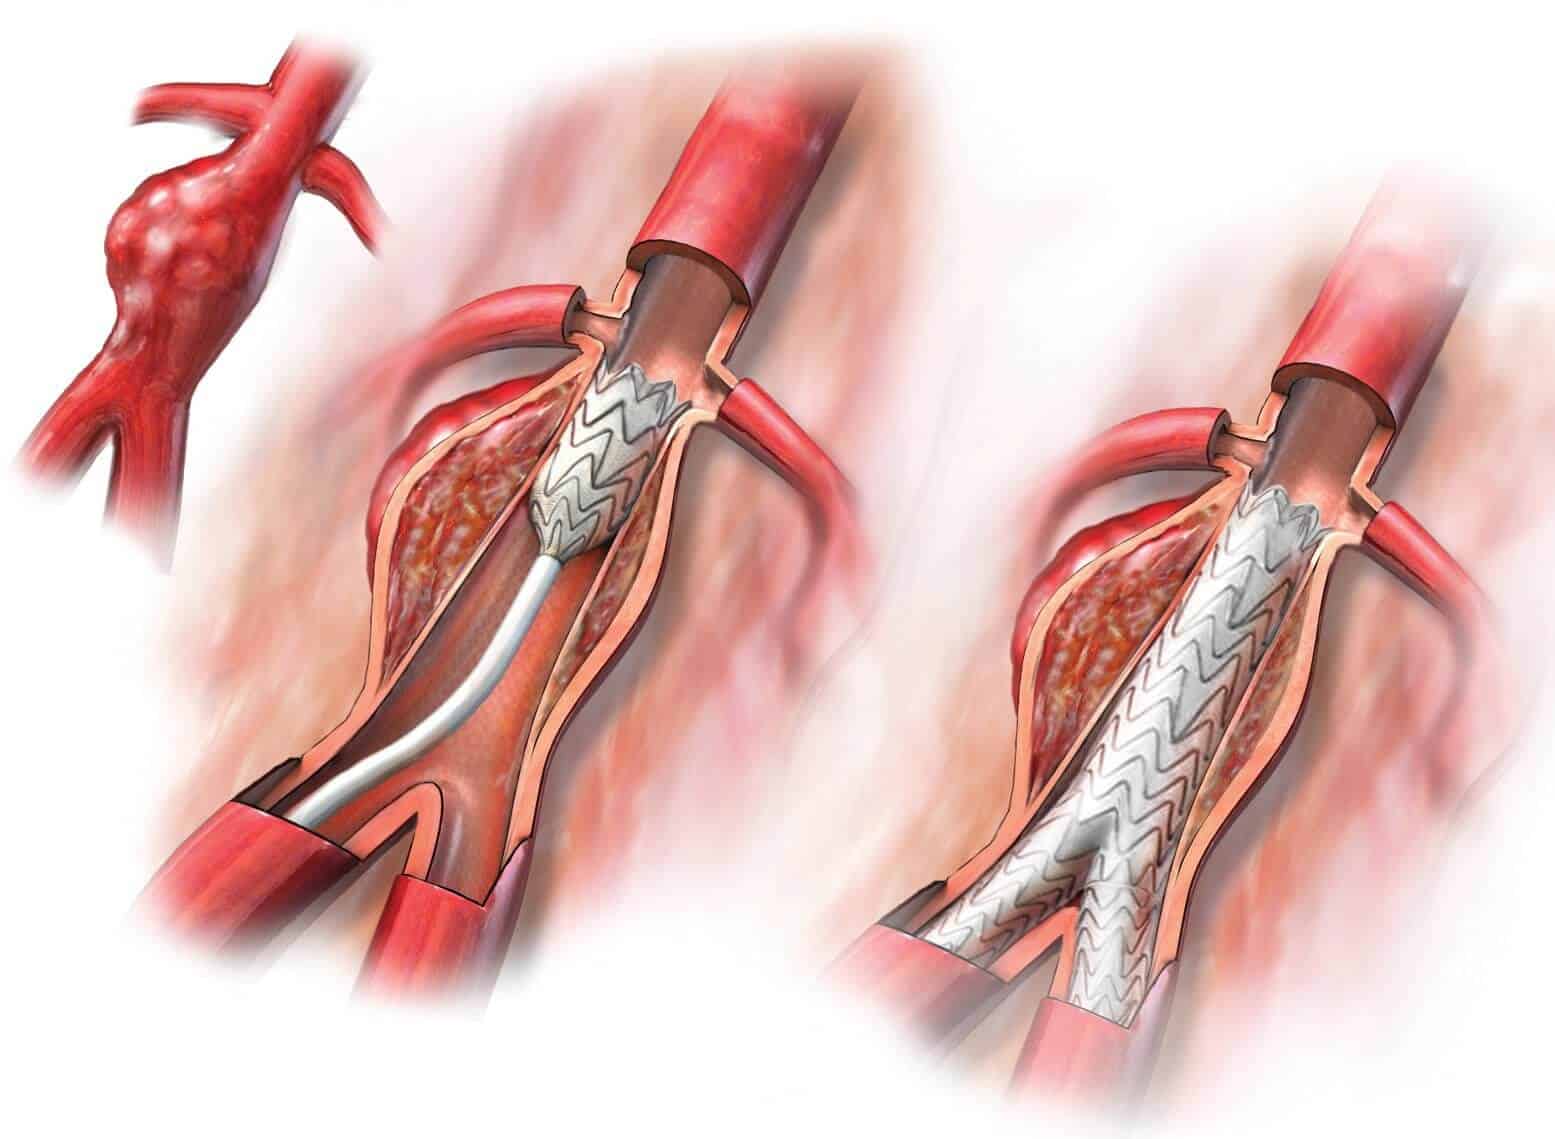

Хроническая окклюзия артерий: причины, симптомы и лечение